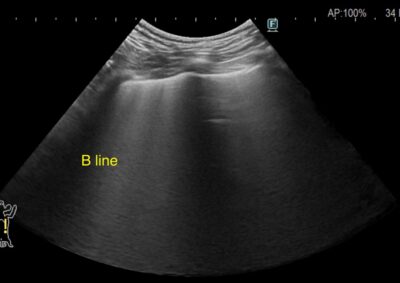

救急・集中治療 注意 ボタンをクリックした先に、治療中および手術中の画像が説明で使用されている場合がございます。 そのような画像に弱い方は閲覧なさらないようお願いいたします。 救急・集中治療 犬の急性膵炎 救急・集中治療 糖尿病合併症(HHS) 救急・集中治療 熱中症 救急・集中治療 糖尿病性ケトアシドーシス 救急・集中治療内視鏡科 食道内異物(ジャーキー) 救急・集中治療 心原性肺水腫 軟部組織外科救急・集中治療 腸閉塞・腸切開 軟部組織外科救急・集中治療 胆嚢粘液嚢腫破裂 救急・集中治療 アナフィラキシーに伴う腹腔内出血 救急・集中治療脳神経科 脊髄梗塞 救急・集中治療内視鏡科 消化管内異物・内視鏡摘出 腫瘍外科救急・集中治療 脾臓腫瘤破裂による腹腔内出血 <1234567> 症例カテゴリー 放射線治療整形外科軟部組織外科脳神経外科内科腫瘍外科救急・集中治療リハビリテーション科腫瘍内科内視鏡科脳神経科呼吸器外科中医・漢方猫の腎移植循環器科